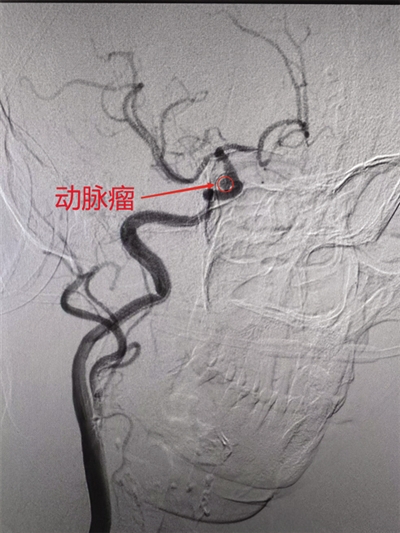

患者脑血管局部影像显示动脉瘤。

患者女性,76岁,因发现左侧肢体活动不利、言语含糊4个多小时入院,头颅磁共振确诊为急性脑梗死。经MDT团队紧急会诊,决定为其行脑血管造影术,以明确脑血管是否狭窄及狭窄程度。通过脑血管造影,不仅清晰发现患者头臂干动脉起始部狭窄、颅内动脉粥样硬化、右侧颈内动脉后交通段存在“定时炸弹”——动脉瘤。此次造影为患者制定更合理的治疗方案提供了科学的依据。